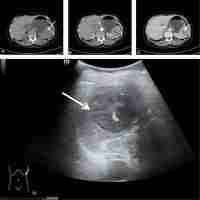

Inflammatory pseudotumor-like follicular dendritic cell tumor of the spleen.